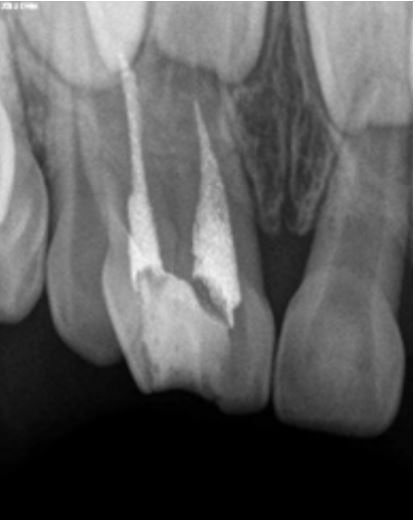

A 5-year-old male patient reported to our clinic with the chief complaint of decayed upper front teeth region. Patient presented with an episode of spontaneous pain which was relieved on medication. Medical history was non-contributory. Clinical examination revealed a geminated deciduous maxillary right central incisor (51, ISO system) having a large crown, showing a groove between non separated crowns on labial surface (Figure 1). It was noted to be non-vital on examination with electric pulp tester (Pulp tester C-pulse, Foshan CICADA Technology, China, input DC 9 V, output 80 V, 90 mA). Radiographic examination revealed two independent pulp chambers and two fused roots but with individual canals within (Figure 2). History, clinical and radiological findings pointed at the diagnosis of chronic irreversible pulpitis and pulpectomy was planned. Local anaesthesia (2% Lidocaine) was administered and rubber dam application was done. Access was achieved from the palatal surface and two canals were located; one, mesial and the other distal. Pulp extirpation and debridement was done by ProTaper Gold rotary files (Dentsply Maillefer, Ballaigues, Switzerland) upto F1. Irrigation of root canal was done with 2.5% sodium hypochlorite and saline. Obturation was done with Metapex (Meta Biomed Co. Ltd, Cheongju, Korea) (Figure 3). Access cavity was restored with glass ionomer cement till the cervical third and final restoration completed with composite.

Figure 2: Radiograph showing two evident roots and two separate pulp chambers.